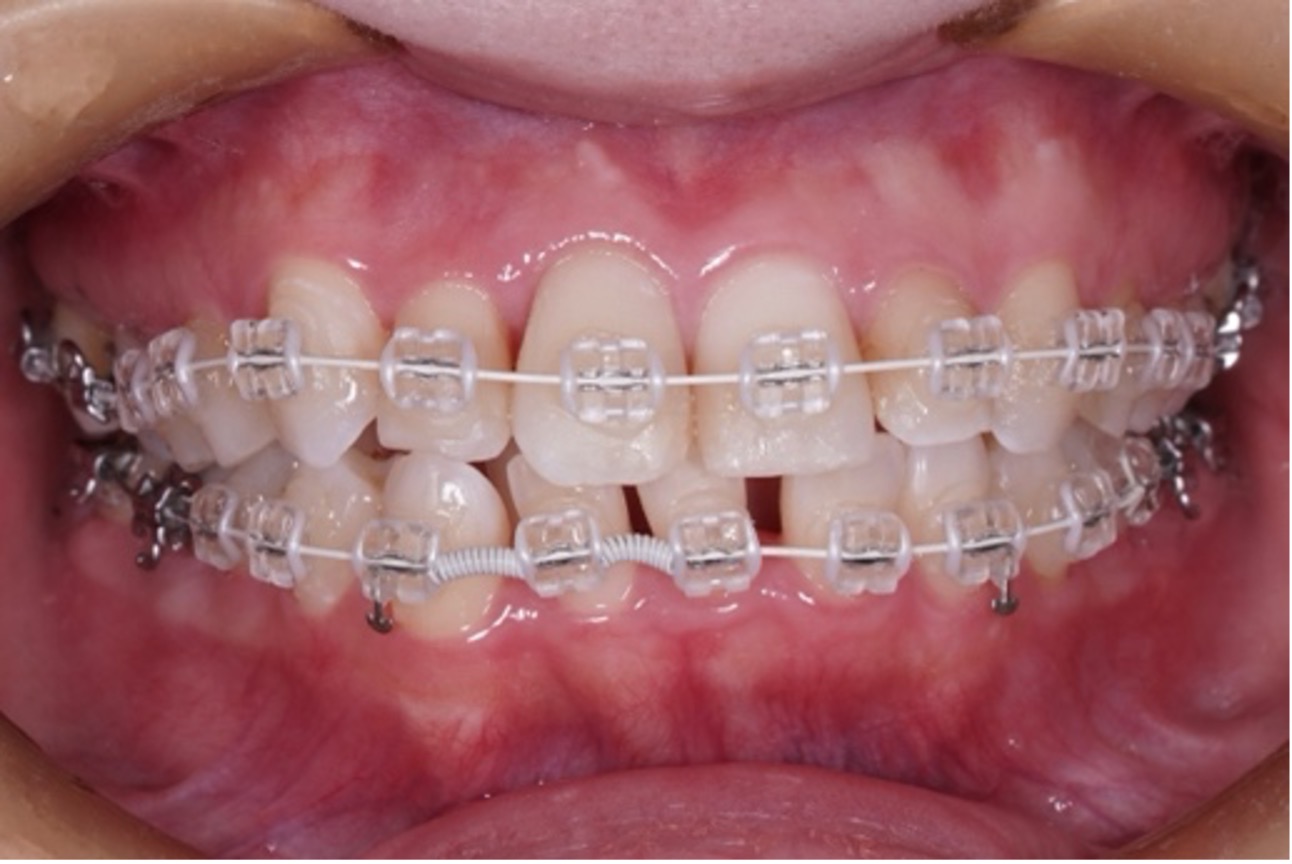

歯の表面または裏側にブラケットを装着し、ワイヤーの力で歯を動かす伝統的な方法です。

現在も多くの矯正歯科で採用されており、精密で確実な歯の移動が可能です。

⚫︎装置が目立ちやすい(※当院ではなるべく目立たないようにセラミックブラケットを使用しています)